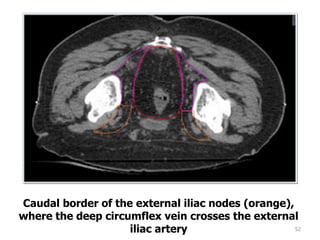

Caudal border of the external iliac nodes (orange),

where the deep circumflex vein crosses the external

iliac artery

52 Caudal border ofthe external iliac nodes (orange), where the deep circumflex vein crosses the external iliac artery